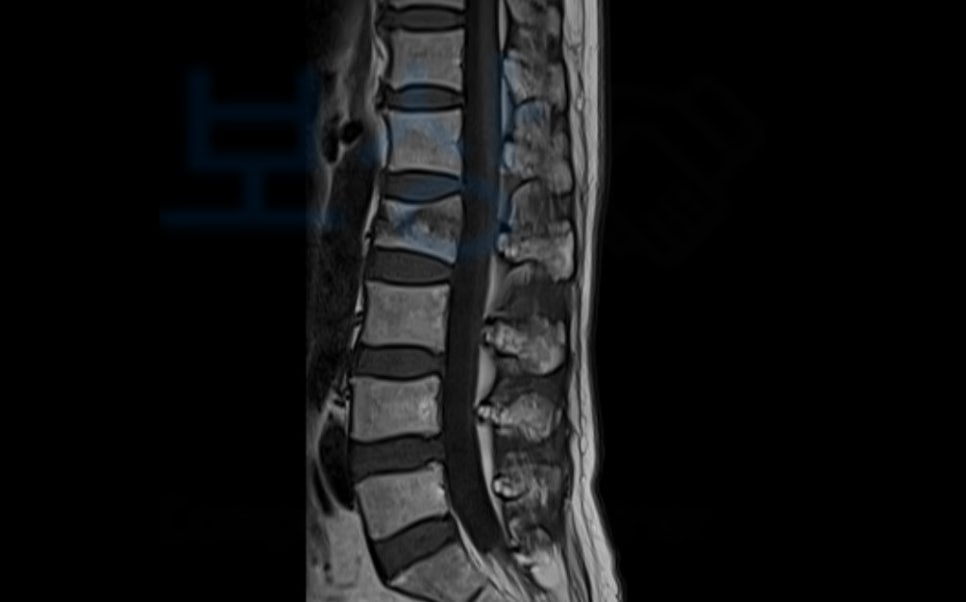

진단을 받으셨꼬 Mri를 찍어보니

요추2번 척추압박골절 확정되었습니다. 주치의는 두달간의 보존치료를 권하였고

가입시기에 따른 약관의 변화와 예상 보상 범위를 말씀드린 후 사건을 수임하여 진행하게 되었는데요, 장해의 잔존을 증명하기 위해서는 의료 전문의의 후유장해 진단서가 필요한데

AMA 후유장해 진단서 발급을 하게 되었습니다. 이 후 손해사정서도 함께 작성하여 각 보험회사에 청구하였는데요,. 역시나 보험회사에서는 압박률과 후만각의 의료자문을 시행하겠다며 보상파트너와 약 한달간의 분쟁을 하였지만

척추에 뚜렷한 기형을 남긴 때 30% 영구장해